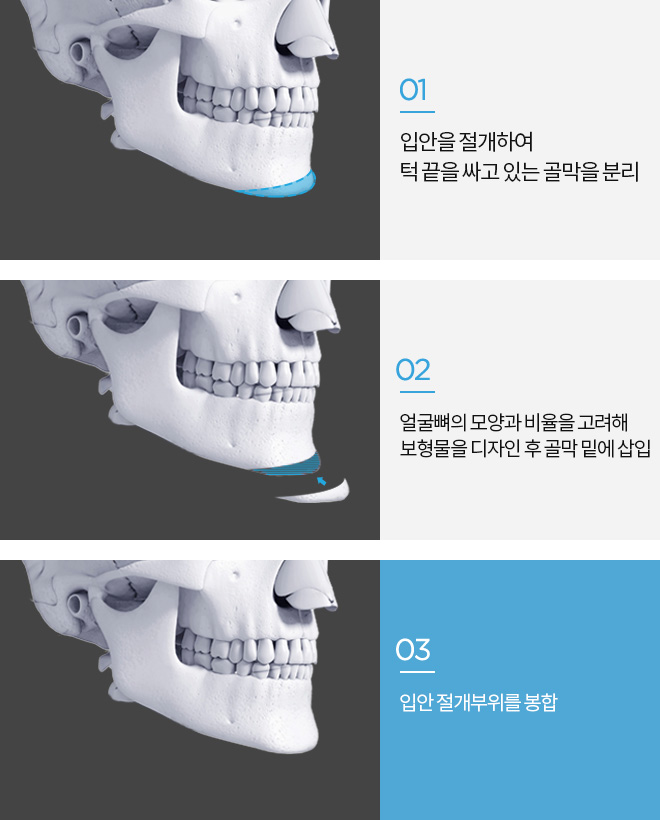

연세로운성형외과의 무턱보형물 수술방법

개개인의 얼굴형에 맞는 보형물로 턱끝에 볼륨을 주어 턱선과 입매개선은 물론 전체적인 얼굴의 비율 개선해 줍니다

무턱보형물

자연스럽게 턱끝 개선

입안 절개를 통해서 흉터걱정이 없기에 매끈하고 자연스러운 턱끝 모양